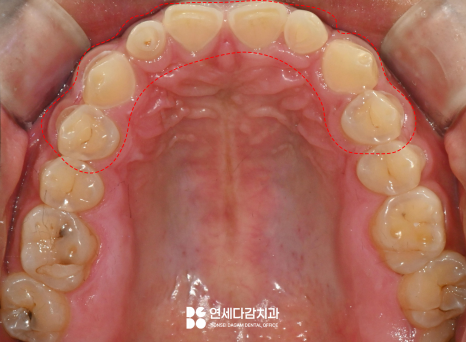

다만 해당 케이스는 환자가

불편한 부위만을 먼저

시행하는 것을 원했습니다.

그에 맞는 계획을 세우기 위해서

우선 치료할 부위를

정밀하게 검진합니다.

이렇게 이가 편평해질 정도로

교모된 곳을 우선 치료하게 됩니다.

충치가 있는 곳도 있었으나

치수에 도달할 정도로

심하게 진행된 상태는 아니었습니다.

따라서 문정동 치과 에서는

크라운 치료만으로

회복을 할 수 있었습니다.